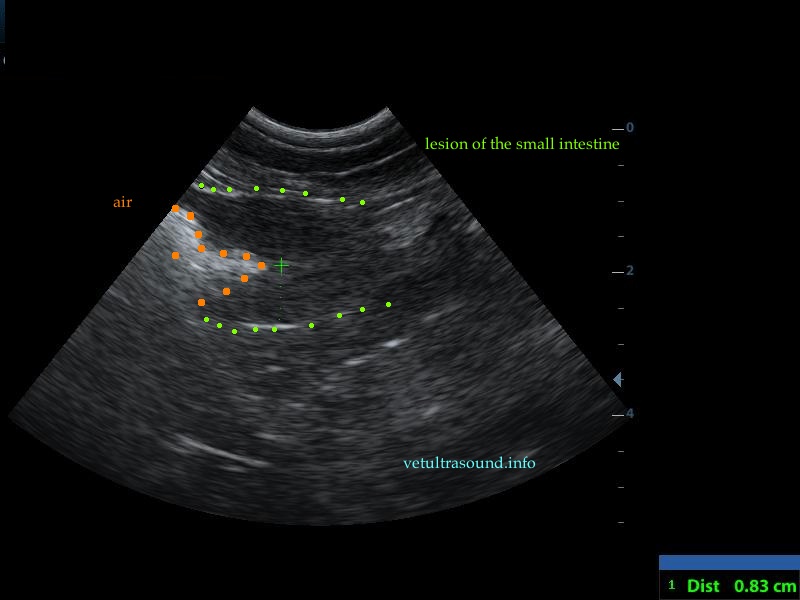

Findings: There was an increase in thickness of a segment of the small intestine, in which the normal layering was lost. This lesion extended for 3 cm(pic1). There was a restriction of the lumen, in this segment(pic2). In other parts of the ileum the muscularis propria was increased in thickness, compared to the thickness of the submucosa and the mucosa(pic3,4). The renal cortex of both kidneys was hyperechoic compared to the echogenesity of the liver and the spleen(pic5). A small amount of ascites was noted. The regional lymphnodes were enlarged and the mesenteric fat, which encircled the lesion of the small intestine, was hyperechoic.

Diagnose: These findings are compatible with alimentary tract lymphoma. There is a possibility that the kidneys are also infiltrated by lymphocytes.